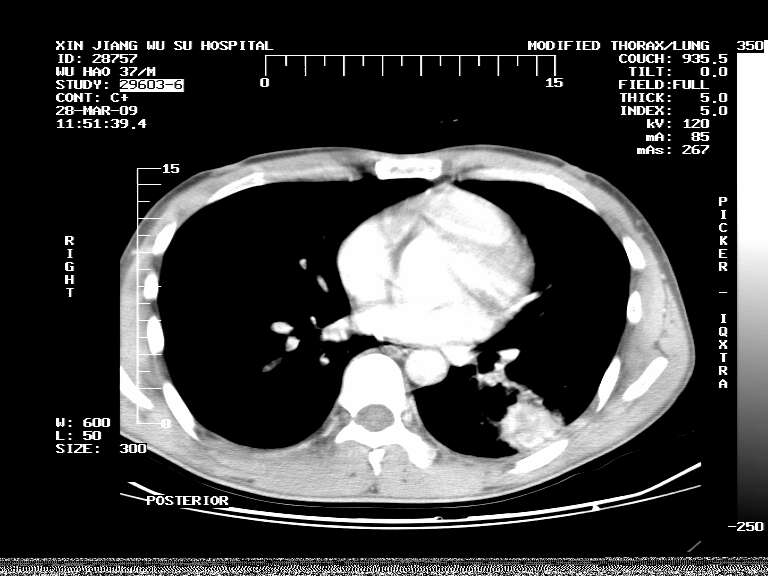

男,37岁,体检胸透发现阴影。

患者体检发现 无症状 左肺下叶占位,边缘模糊,可见血管聚束、分叶、胸膜牵拉,增强呈不均匀性强化。 首先考虑左肺下叶周围型肺癌,建议穿刺活检。

患者体检发现 无症状 左肺下叶占位,边缘模糊,可见血管聚束、分叶、胸膜牵拉,增强呈不均匀性强化。 首先考虑左肺下叶周围型肺癌,建议穿刺活检。支持!

左肺下叶见一结节病变,边缘欠清不光滑,与胸膜粘连且胸膜局限性增厚,注药后呈环形强化,动脉期壁呈明显点环状强化,静脉期壁强化减低,中心密度低无强化,灶周无明显的卫星灶和水肿区(晕征)---考虑周围性肺癌,不除外感染性病变,建议穿刺活检。

病灶强化太明显,病人较年轻。考虑炎性假瘤与周围型肺癌鉴别,以前者可能性,建议抗炎治疗后复查。